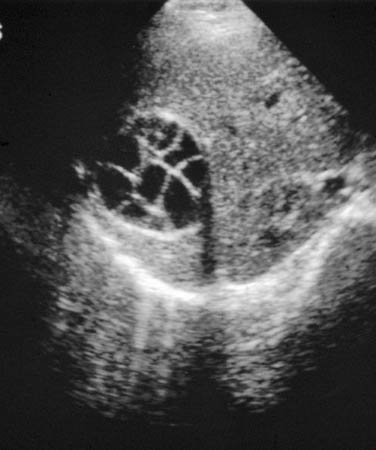

A ultrassonografia abdominal pode detectar cistos hidáticos (por exemplo, equinococose do fígado).

A Organização Mundial da Saúde (OMS) classifica os estádios do Echinococcus granulosus como ativo versus inativo, e essa classificação guia a terapia. CE1 é uma lesão cística anecoica unilocular com um sinal duplo. CE2 é um cisto multiloculado no formato de "colmeia semelhante a roseta" (esse é um cisto-mãe preenchido com cistos filhos). O CE1 e o CE2 são considerados cistos ativos, geralmente férteis, que contêm protoscólices vivos. CE3a é um cisto com membranas soltas (sinal do nenúfar), enquanto o CE3b tem cistos filhos em uma matriz sólida. Eles são considerados cistos no estádio transicional, em que a integridade do cisto foi comprometida pelo hospedeiro ou pela quimioterapia. Um cisto com conteúdo hipoecoico/hiperecoico heterogêneo e sem cistos filhos é o estádio CE4, enquanto os cistos calcificados são considerados CE5. Os CEs dos tipos 4 e 5, que são inativos, normalmente, perderam a fertilidade e são degenerativos.[38]

[Figure caption and citation for the preceding image starts]: Equinococos do fígado com cisto filho na ultrassonografia: cistos multivesiculares, multiloculados, nos quais o cisto filho preenche completamente o cisto-mãe unilocular; o cisto produz uma estrutura semelhante a uma rodaDo acervo da Dra. Christina Coyle e do Dr. Maheen Saeed; usado com permissão [Citation ends].

Resultado

cistos hidáticos